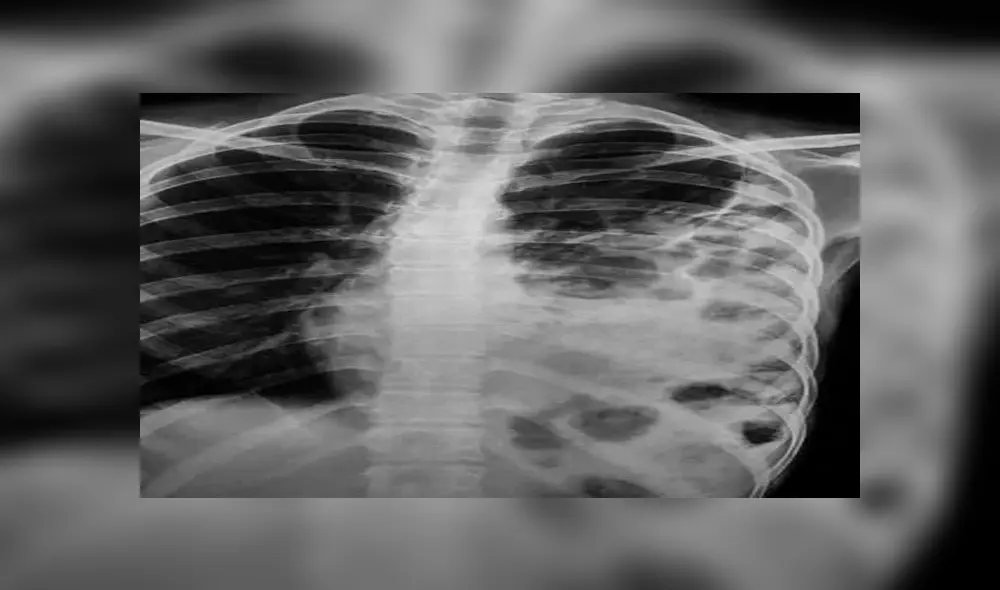

El joven fue sometido a varios estudios médicos para determinar las causas de su padecimiento. Los galenos informaron que luego de realizarle los análisis, estos dieron como resultado que el paciente sufría de una hernia diafragmática congénita.

“La hernia diafragmática congénita” se trata de una abertura en el abdomen que permite que los órganos abdominales se trasladen hasta la cavidad torácica.

A causa de este mal, el chico debió ser sometido a una cirugía laparoscópica con el objetivo de mover las vísceras a su lugar original y así suturar la abertura.